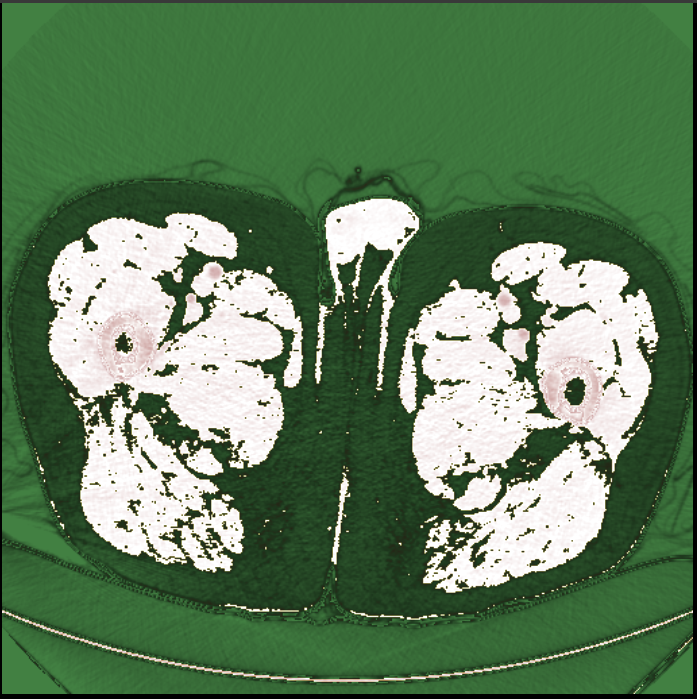

- Currently using **incorrect** mapping of

const ctx = canvas.getContext( '2d' ) const imageData = ctx.createImageData( 512, 512 ) const pixelData = getPixelData( dataSet ) let rgbaIdx = 0 let rgbIdx = 0 let pixelCount = 512 \* 512 for ( let idx = 0; idx < pixelCount; idx++ ) { imageData.data[ rgbaIdx ] = pixelData[ rgbIdx ] imageData.data[ rgbaIdx + 1 ] = pixelData[ rgbIdx + 1 ] imageData.data[ rgbaIdx + 2 ] = 0 imageData.data[ rgbaIdx + 3 ] = 255 rgbaIdx += 4 rgbIdx += 2 } ctx.putImageData( imageData, 0, 0 )

图1.不正确的映射